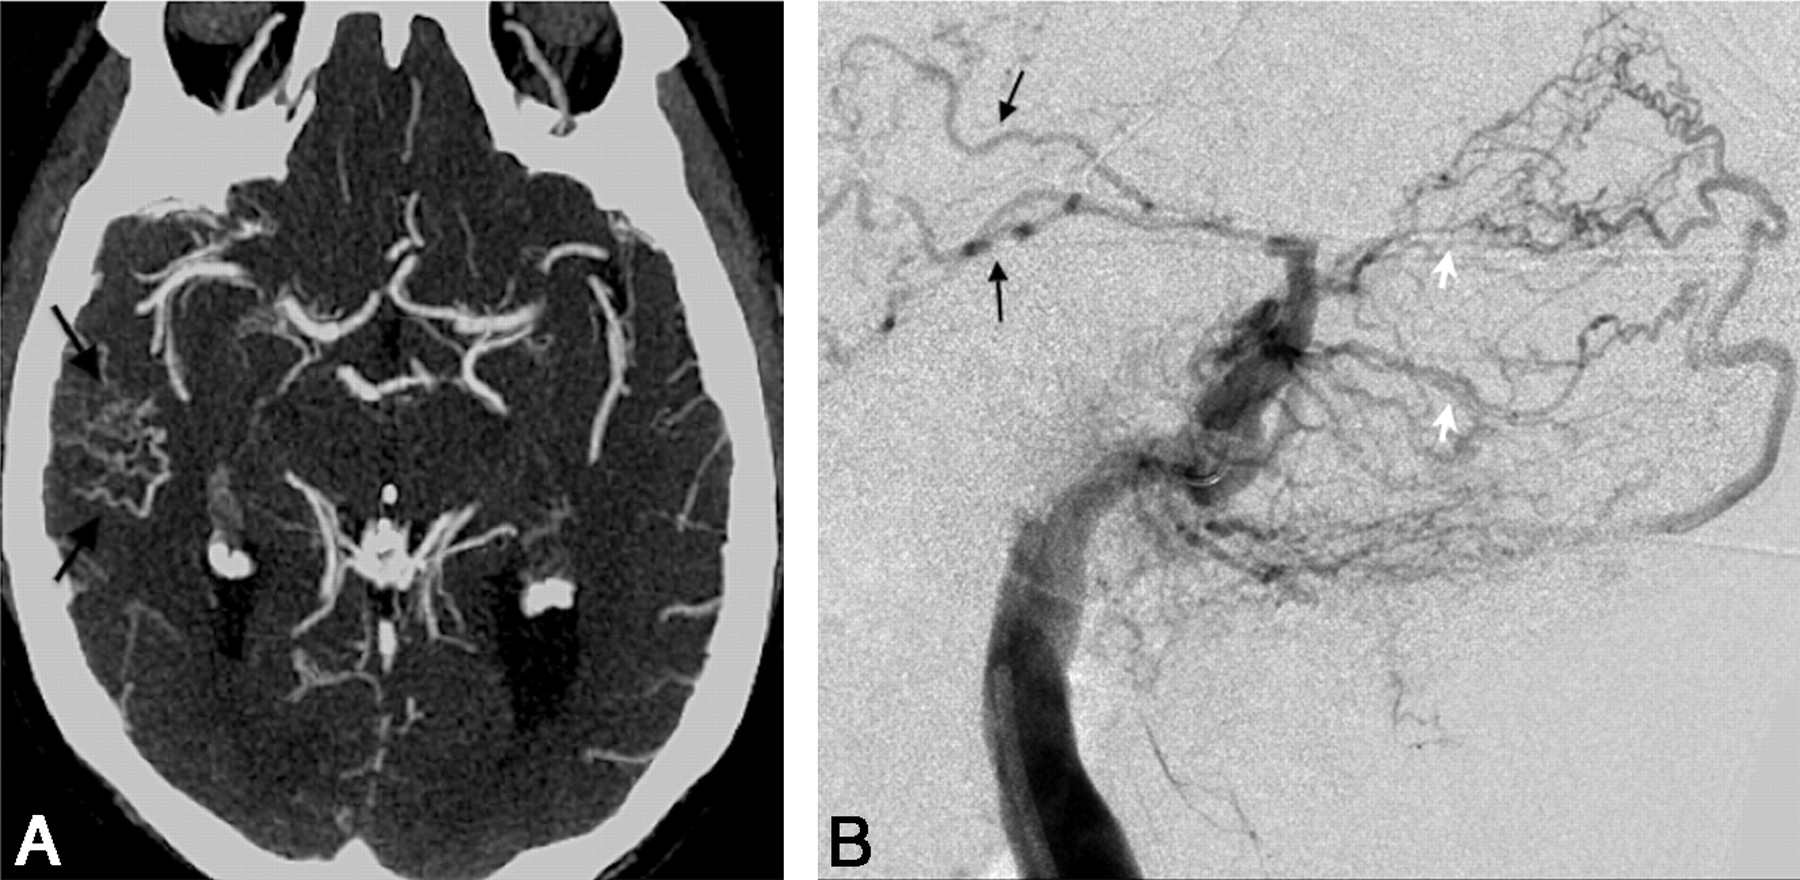

A, Axial 3-mm-slab MIP from CTA in patient 7 illustrates a cluster of abnormally prominent, tortuous, and numerous veins overlying the right temporal lobe (black arrows). These are dilated cortical venous efferents, which are thought to confer increased risk of hemorrhage. B, DSA, right external carotid injection, venous phase, in a lateral projection in the same patient as in A, demonstrates retrograde cortical or leptomeningeal draining veins (black arrows) in the right temporal region in this Cognard IIa+b fistula. Note multiple arterial feeders arising from the occipital artery (white arrows).

A, Coronal 3-mm-slab MIP from CTA in patient 3 with a right transverse sinus DAVF, predominantly supplied by right occipital, middle meningeal, and marginal tentorial branches; some supply from the left internal carotid is also seen, as described below. This case illustrates the “asymmetric jugular attenuation” sign, which is easily appreciated when the R and L IJVs are compared. The attenuation of the R IJV is 402 HU, and the L IJV is 318 HU. B, DSA, late arterial phase, left internal carotid injection in an anteroposterior projection in same patient as in A. Fistula supply from small left internal carotid artery dural and tentorial branches (black arrows) contributes to early opacification of the right sigmoid sinus and IJV (note the catheter near the jugular bulb). Due to the arteriovenous shunt surgery and drainage pattern, iodinated contrast preferentially fills the right jugular vein (black arrowheads) and leads to an asymmetric right-sided increase in CT attenuation, which is seen in A.